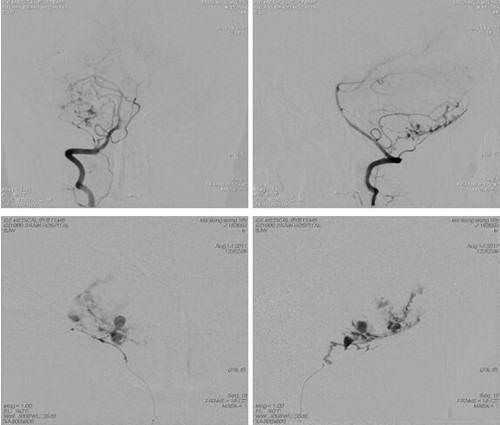

术中造影见右侧小脑异常染色,呈类圆形,大小约

用微导管经右侧椎动脉V3段分支向肿瘤首先注入碘油3ml弥散入肿瘤染色区域,后用10% GLUBRAN2 0.4mL弥散至肿瘤供血微小血管及部分主干,复查造影显示肿瘤栓塞约90%。